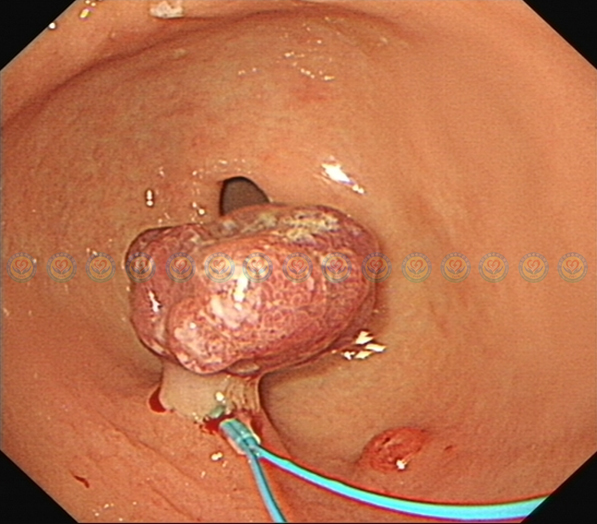

进镜至胃窦,幽门处见肿块嵌顿。

近观,有肿块嵌顿于幽门口,表面糜烂渗血,有粗蒂与胃窦大弯侧相连。

肿块退回胃内,其直径在3cm以上,且存在粗蒂,考虑内有粗大滋养血管。直接电切有较高出血风险。

内镜下送入尼龙圈结扎器,结扎肿块蒂部。